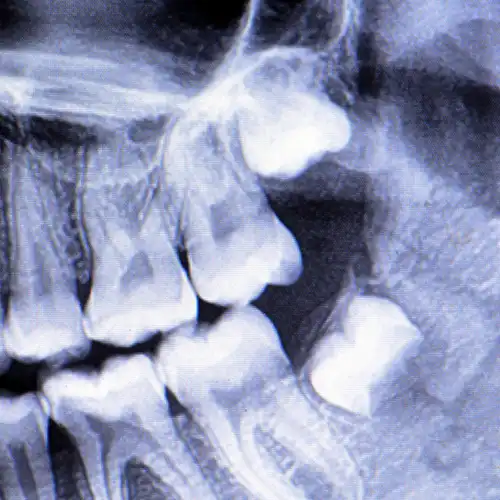

Tooth loss can be frustrating, but it doesn’t have to take away your ability to eat, speak, or express joy with a smile that looks and feels completely natural. At Yobi Family Dental, we provide denture solutions that are practical, comfortable, and crafted to help you feel and smile like yourself again.

Whether you’re missing a few teeth or need a full denture, we’re here to help restore the comfort, balance, and confidence you deserve. Each denture is carefully crafted around your unique needs and smile, so eating and speaking feel natural again. During your consultation, we’ll take the time to listen to your goals, answer your questions, and guide you toward the denture option that’s the best fit for you.

Some patients choose to pair their dentures with dental implants placed by a specialist, which can provide added stability and comfort. If that option is right for you, Yobe Family Dental can tailor a treatment plan just right for your needs and walk you through to a final result that’s secure, natural, and feels like your own smile again.